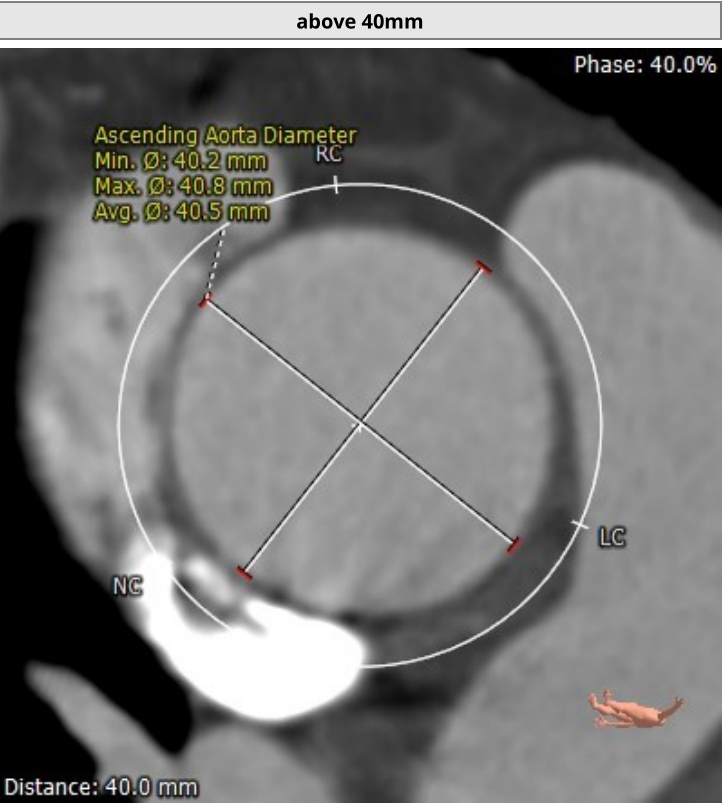

该名患者为Type 0型二叶瓣,右冠窦轻度钙化。瓣环最短径为20.0mm,最长径为27.7mm,平均瓣环直径为23.8mm。升主动脉较宽,平均直径40.5mm。左冠开口高度13.6mm,右冠开口高度16.3mm,冠脉阻塞风险低。外周血管钙化轻,入路情况较佳。FEops分析推荐匹配26mm瓣膜。